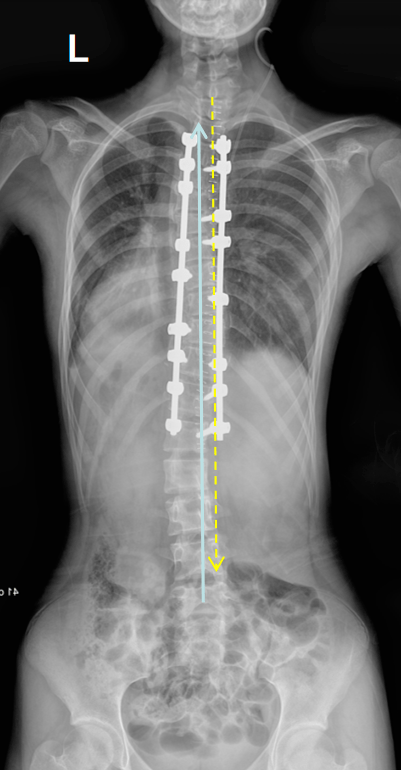

手術後

提早預防和篩查是防止青少年脊柱側彎的關鍵。那麼怎麼才能提早發現呢?側彎篩查六步法,家長、老師們可以補補課啦!